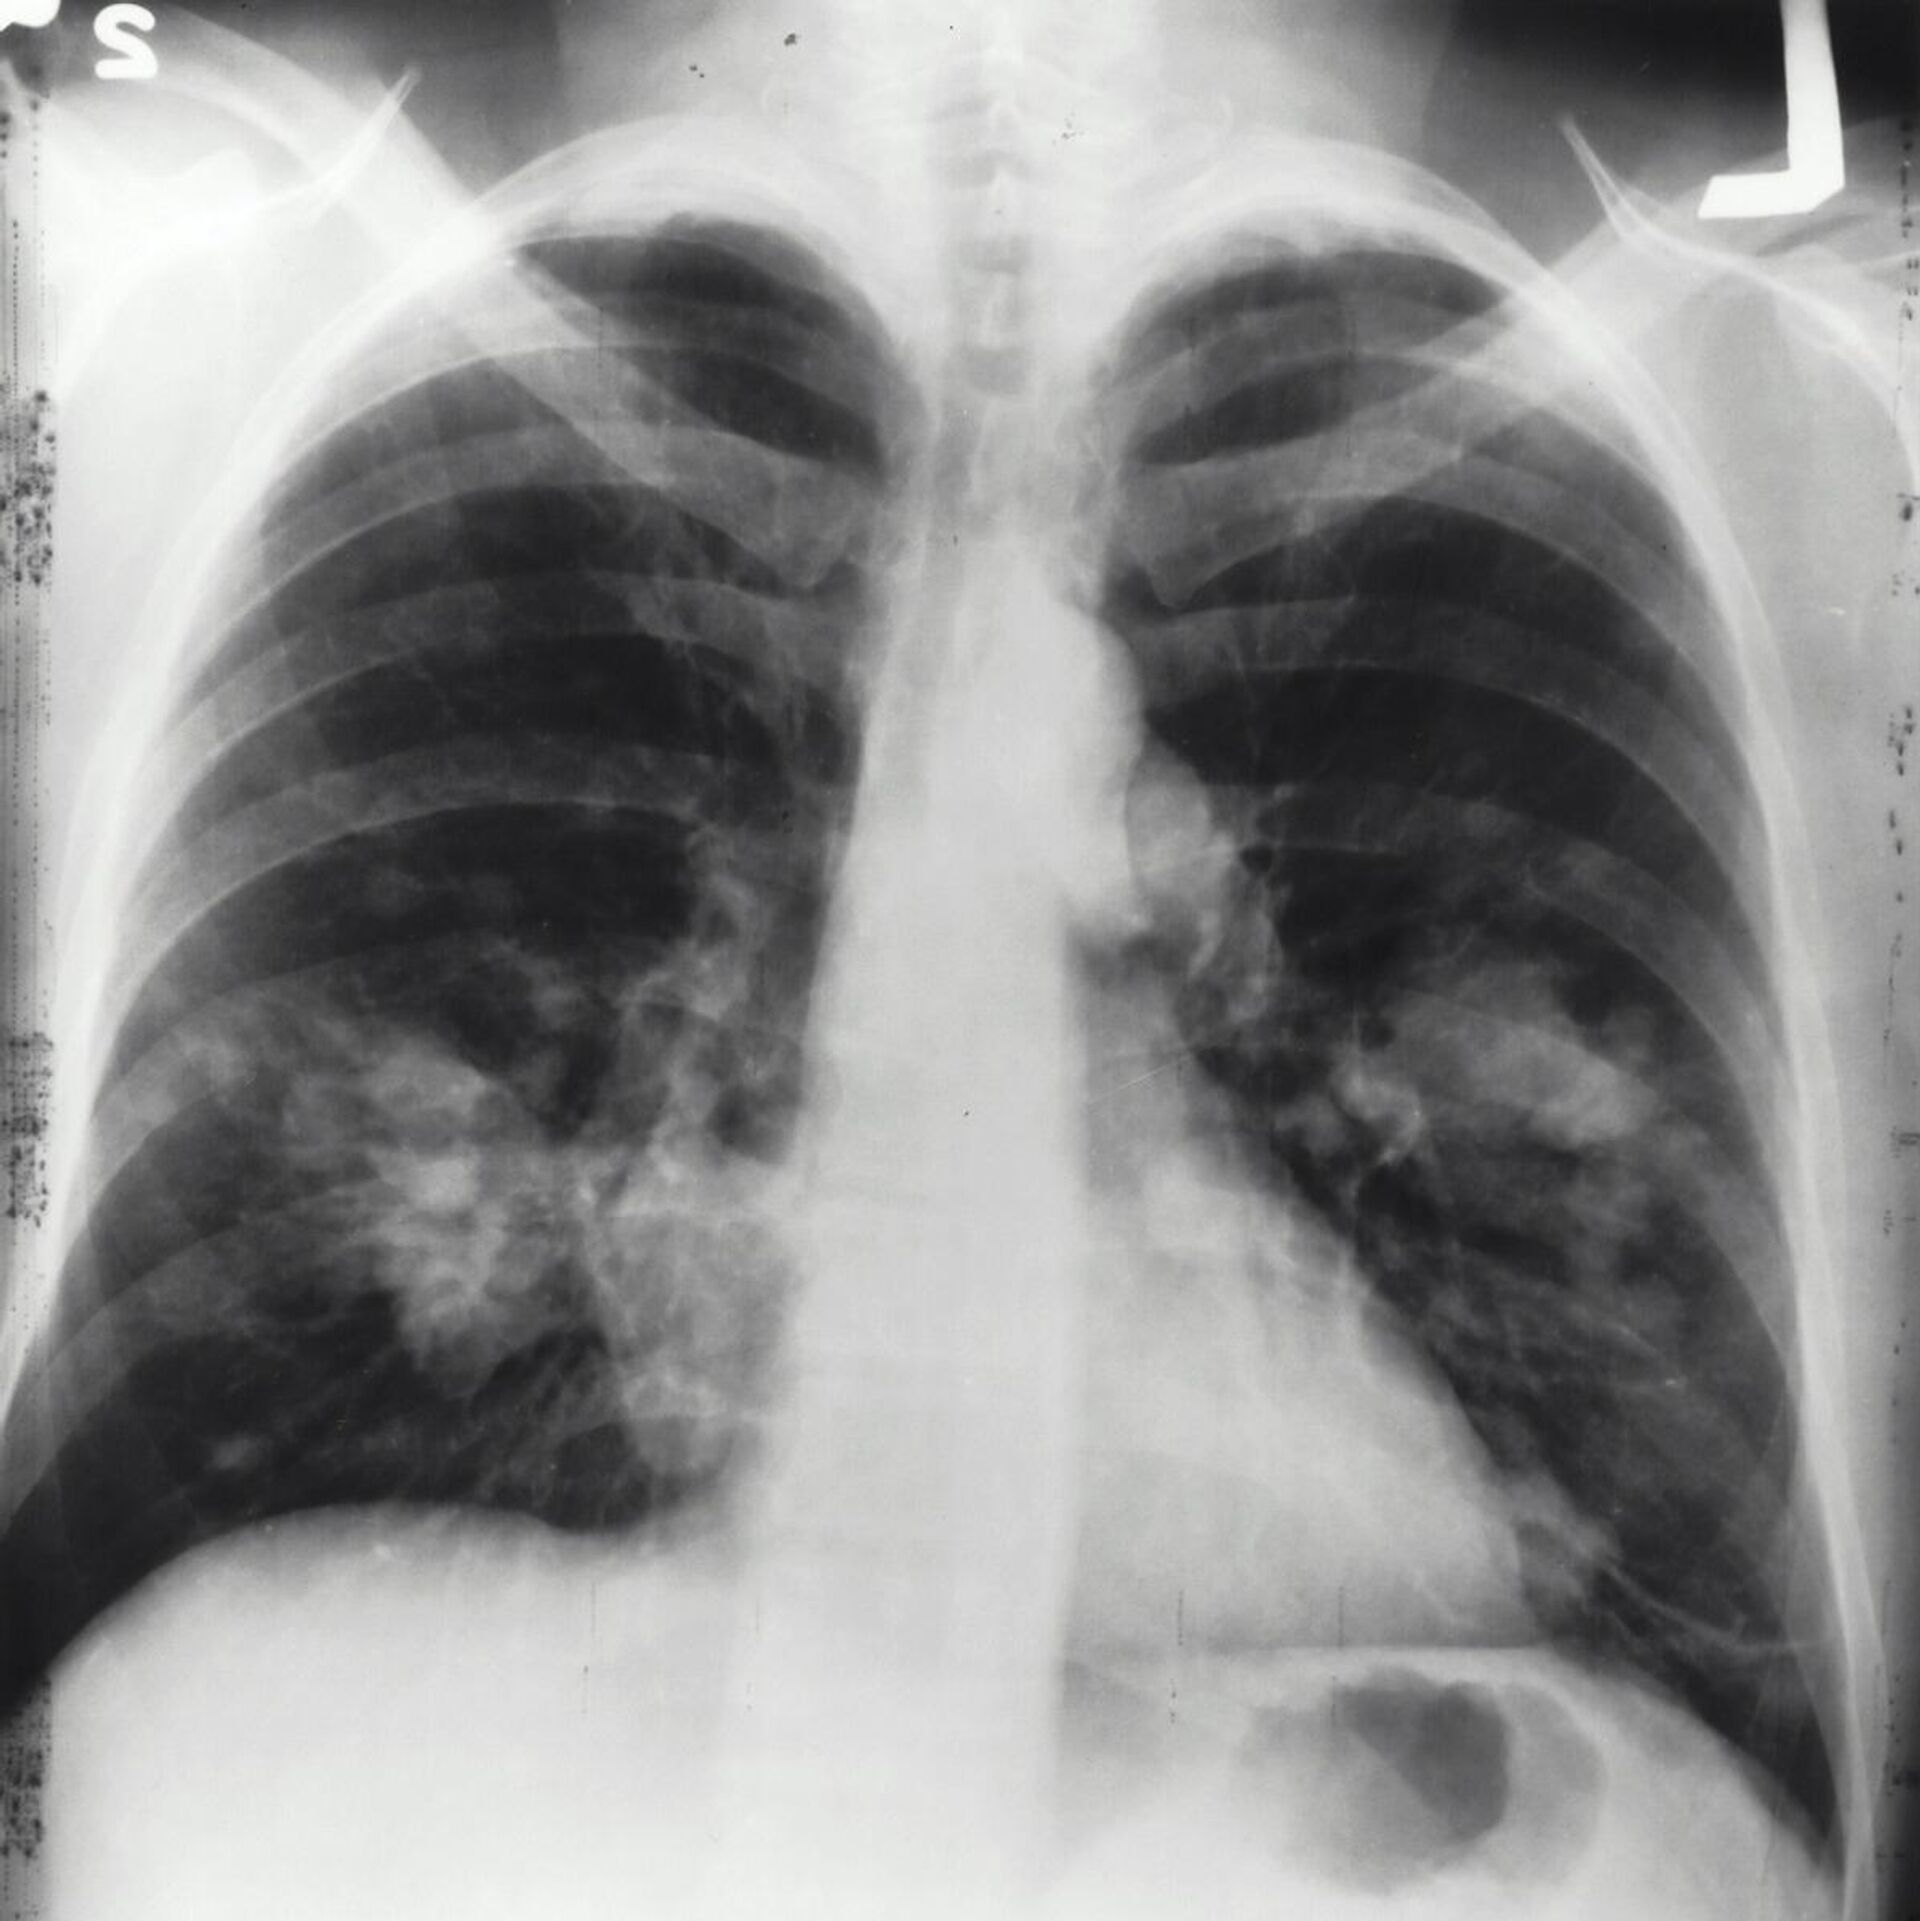

21:23 GMT 15.02.2025 (تم التحديث: 05:02 GMT 16.02.2025) كشفت دراسة جديدة عن تزايد مقلق في حالات الإصابة بسرطان الرئة بين غير المدخنين، خاصة في مناطق شرق آسيا وبالأخص في الصين، وهو من أكثر الأمراض فتكا، ويتسبب في ما يقارب مليوني وفاة سنويا.

ويُرجع الباحثون هذه الظاهرة، إلى تزايد مستويات التلوث البيئي، وتأثيره السلبي على الصحة العامة.

واستندت الدراسة إلى بيانات من المرصد العالمي للسرطان (GLOBOCAN) 2022، بالإضافة إلى سجلات سابقة تغطي الفترة بين عامي 1988 و2017، والتي أظهرت أن سرطان الغدة الدرقية هو النوع الأكثر انتشارا من سرطان الرئة عالميا، إذ يمثل 45.6% من الحالات لدى الرجال، و59.7% لدى النساء، ويعد هذا النوع من السرطان أكثر شيوعا بين غير المدخنين، على الرغم من إمكانية ارتباطه بالتدخين أيضا، وفقا

لموقع "Science Alert".

كما كشفت الدراسة عن اتجاه متزايد في حالات سرطان الرئة بين الأشخاص الذين لم يدخنوا أبدا، مما يستوجب التعامل مع هذه الظاهرة بجدية، إلى جانب الجهود المستمرة لمكافحة التدخين وتقليل معدلاته عالميا.

وأكد الباحثون أن سرطان الرئة لدى غير المدخنين، أصبح في الوقت الحالي هو السبب الخامس الأكثر شيوعا للوفيات المرتبطة بالسرطان على مستوى العالم، وهو يظهر بشكل شبه حصري على هيئة سرطان غدي، ويُلاحظ بشكل أكبر لدى النساء والسكان الآسيويين.

وخلصت الدراسة إلى أن أحد الأسباب الرئيسية لهذا الاتجاه التصاعدي، هو ارتفاع مستويات تلوث الهواء، إذ أثبتت العديد من الدراسات السابقة وجود علاقة وثيقة بين سرطان الغدة وتلوث الهواء.

وبرزت مناطق شرق آسيا، خاصة الصين، كأكثر المناطق تأثرا بسبب رداءة جودة الهواء فيها، مما يزيد من خطر الإصابة بهذا النوع من السرطان.

وبينما تتراجع نسبة المدخنين عالميا، فيبدو أن التلوث البيئي بات يشكل تهديدا صحيا متزايدا، إذ يتبين أنه عامل لا يرتبط باختيارات نمط الحياة الشخصية، بل يرتبط بالممارسات البيئية العالمية التي تؤثر على جودة الهواء الذي نتنفسه جميعا.

وشدد معدو الدراسة على أهمية جمع البيانات وتحليلها باستمرار لفهم كيفية تطور سرطان الرئة بمرور الوقت، مما قد يساعد العلماء في تطوير استراتيجيات أكثر فاعلية لمواجهة هذا المرض القاتل، وأوصت الدراسة بضرورة تنفيذ سياسات صارمة للحد من تلوث الهواء، إلى جانب تعزيز حملات مكافحة التدخين، بهدف الحد من انتشار المرض، وحماية الأجيال القادمة من خطره المتزايد.